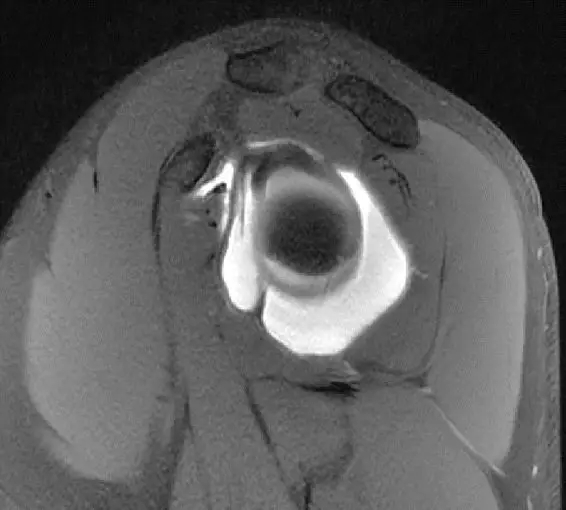

这是一个肩关节造影的磁共振片子,包括肩胛下肌,冈下肌,冈上肌

这张片子是肩胛下肌,上盂唇,冈上肌,冈下肌